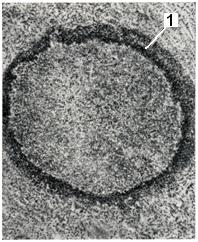

Рис. 1.

Острый абсцесс. Участок ткани, инфильтрированный гнойным экссудатом. Скопление лейкоцитов по периферии абсцесса (1).

В начальном периоде формирования абсцесса инфильтрируется воспалительным экссудатом и лейкоцитами ограниченный участок ткани. Постепенно под влиянием ферментов лейкоцитов ткань подвергается расплавлению, и образуется полость, заполненная гнойным экссудатом. Форма полости может быть как простой округлой, так и сложной, с многочисленными карманами.

Стенки абсцесса в ранней стадии его формирования покрыты гнойно-фибринозными наложениями и обрывками некротизированных тканей. В дальнейшем по периферии абсцесса развивается зона демаркационного воспаления, составляющий ее инфильтрат служит основой для формирования пиогенной мембраны, образующей стенку полости (рис. 1). Пиогенная мембрана представляет собой богатый сосудами слой грануляционной ткани. Постепенно в той ее части, которая обращена в сторону окружающих абсцесса тканей, происходит созревание грануляций. Таким образом, если абсцесс приобретает хроническое течение, в пиогенной мембране образуются два слоя: внутренний, обращенный в полость и состоящий из грануляций, и наружный, образованный зрелой соединительной тканью (рис. 2).